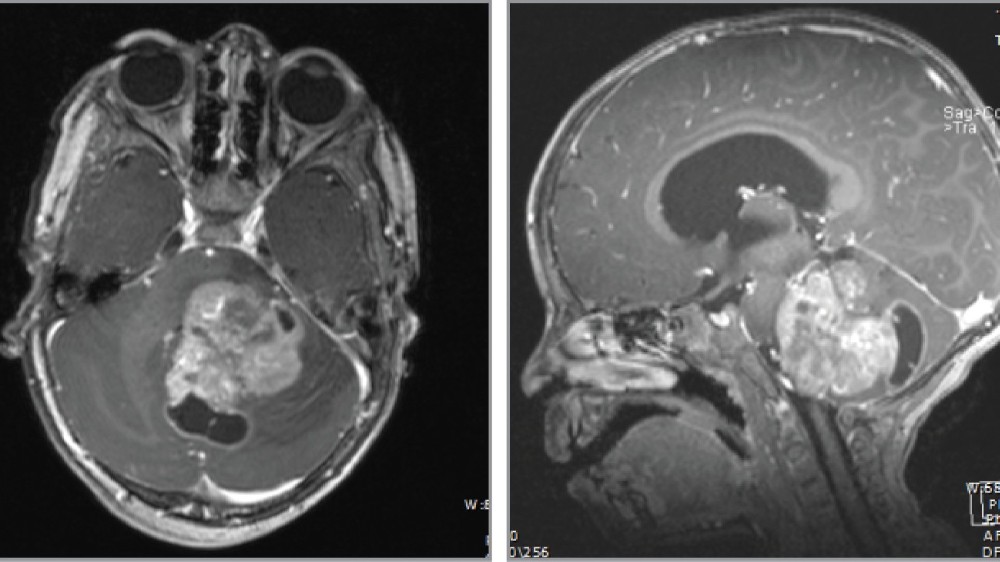

早期 DIPG 的特徵通常是局部異常細胞生長,並局限於腦橋內,通常是透過 MRI 影像檢測到。在此早期階段,症狀可能較輕微、不顯著,而且容易被誤認為其他較不嚴重的疾病。

腫瘤大小: 影像掃描通常小於 2 公分。